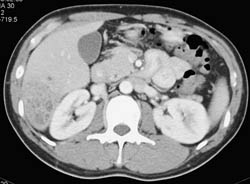

Liver Abscess